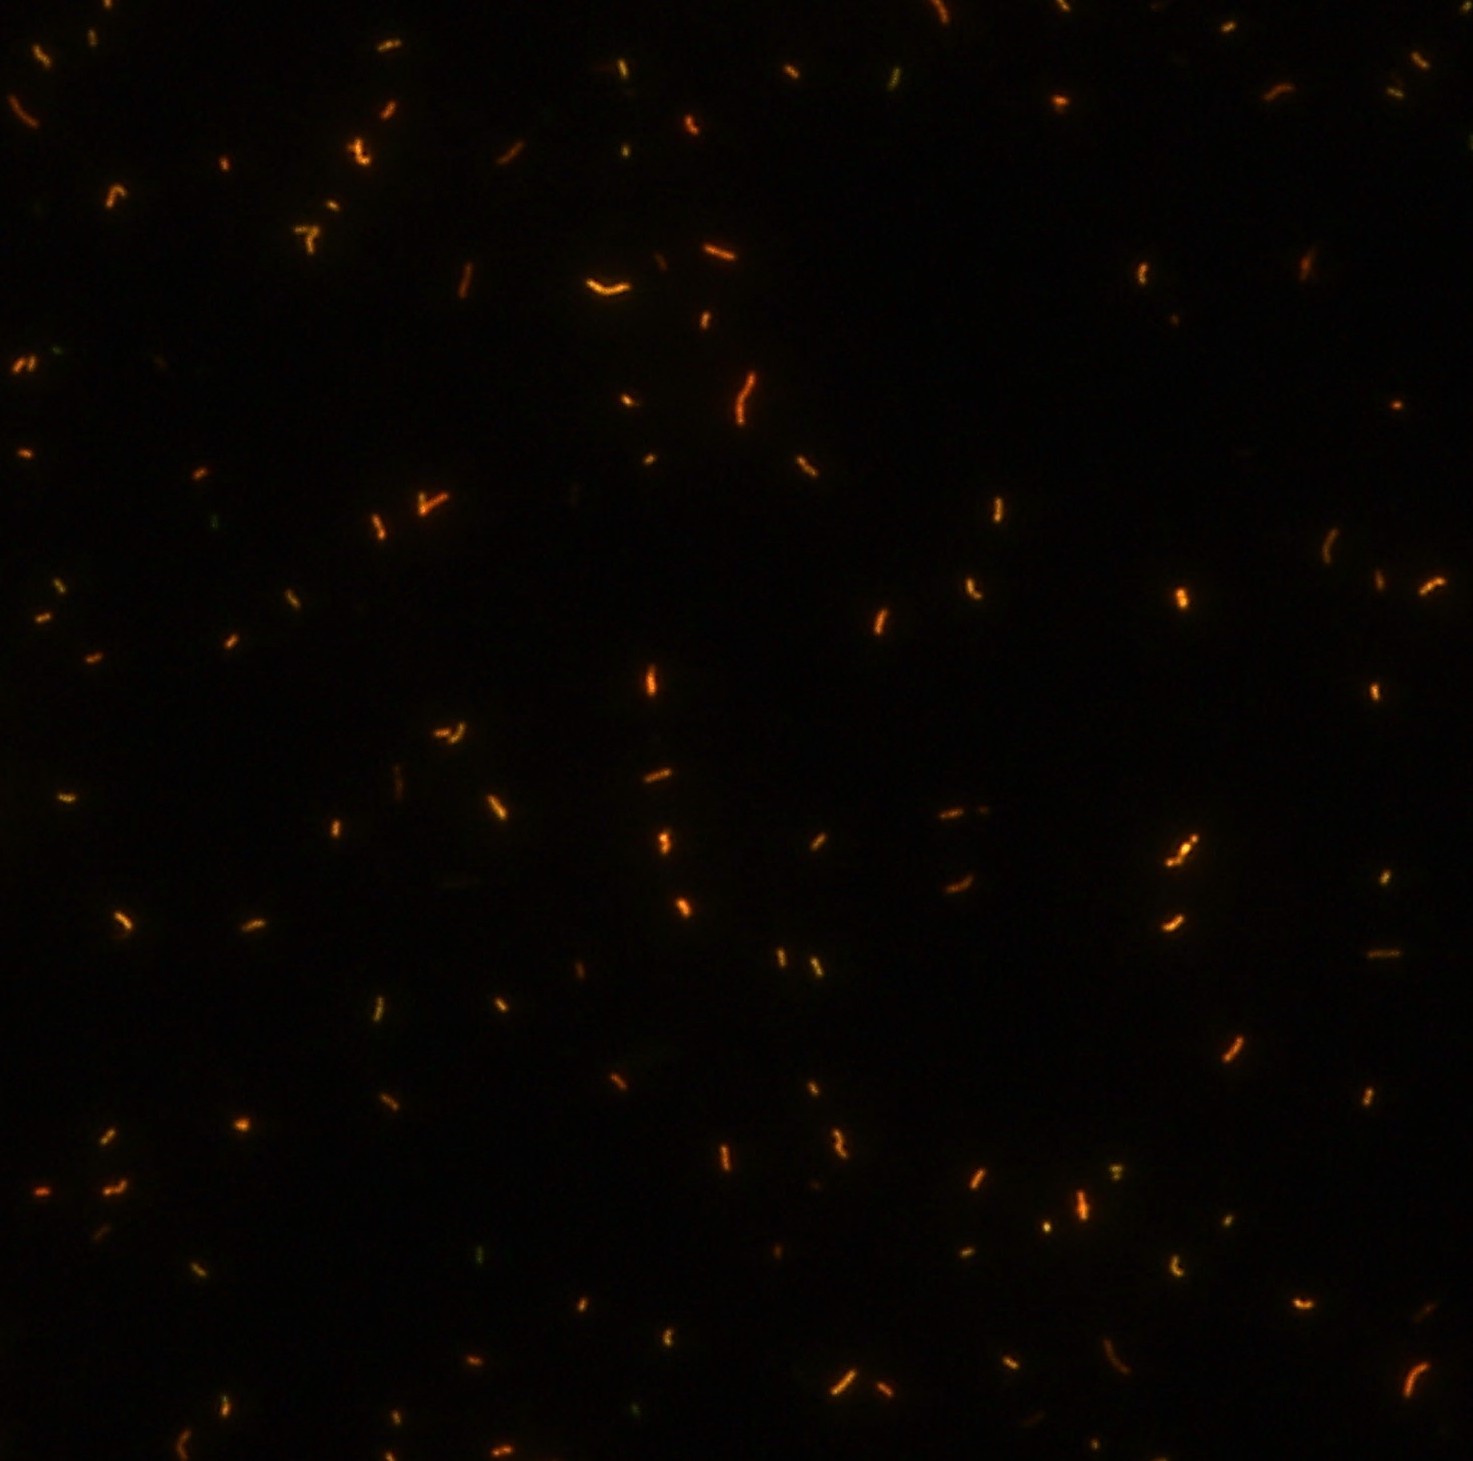

染色結(jié)果 (熒光法×400)

顯微染色技術(shù)是檢測(cè)結(jié)核桿菌方法之一。分枝桿菌細(xì)胞壁中含有分枝菌酸,其可以與染料牢固結(jié)合,具有“抗酸性”的特征。熒光染料金胺-羅丹明在染色中與抗酸生物細(xì)胞壁內(nèi)的分枝菌酸相結(jié)合,并耐受酸醇(脫色劑)清洗脫色。反染色劑高錳酸鉀被用來(lái)顯出染色生物。AFB(熒光)染色試劑盒設(shè)計(jì)既可用于自動(dòng)染色機(jī),也可用于手工染色。產(chǎn)品穩(wěn)定性好,染色效果佳。

用于分枝桿菌、諾卡菌等細(xì)菌抗酸染色,包括熒光染色。